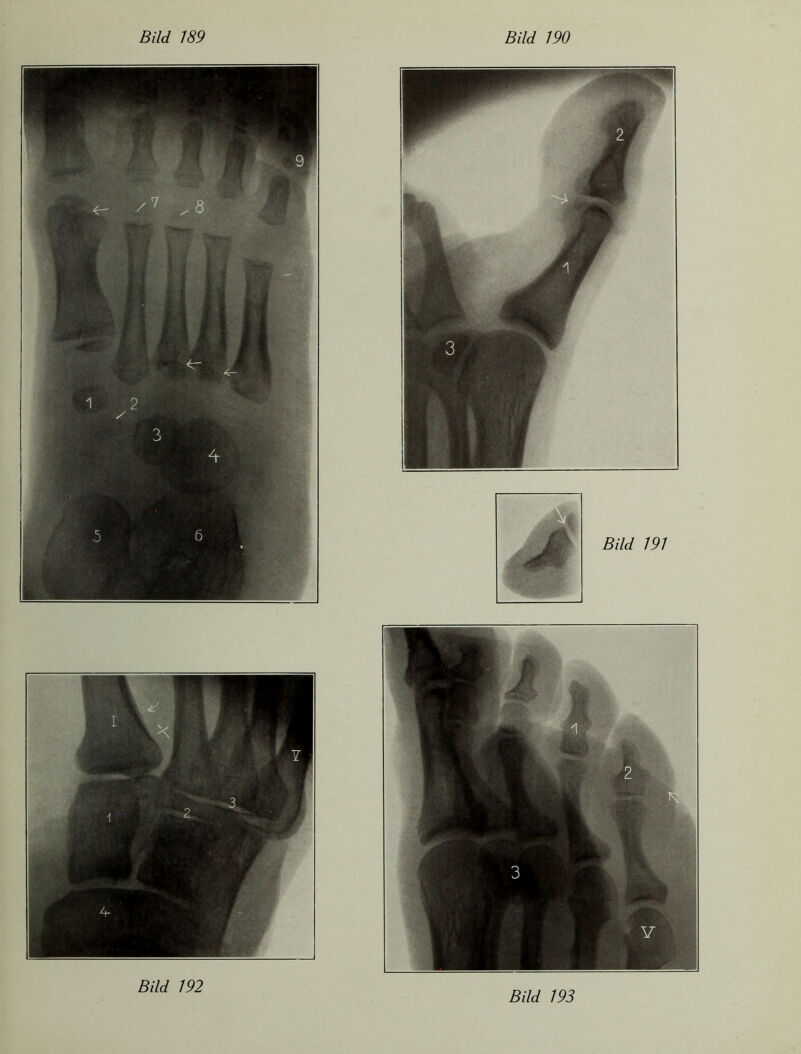

Atlas typischer Röntgenbilder vom normalen Menschen : ausgewählt und erklärt nach chirurgisch-praktischen Gesichtspunkten, mit Berücksichtigung der Varietäten und Fehlerquellen, sowie der Aufnahmetechnik / von Rudolf Grashey.

Credit: Atlas typischer Röntgenbilder vom normalen Menschen : ausgewählt und erklärt nach chirurgisch-praktischen Gesichtspunkten, mit Berücksichtigung der Varietäten und Fehlerquellen, sowie der Aufnahmetechnik / von Rudolf Grashey. Source: Wellcome Collection.